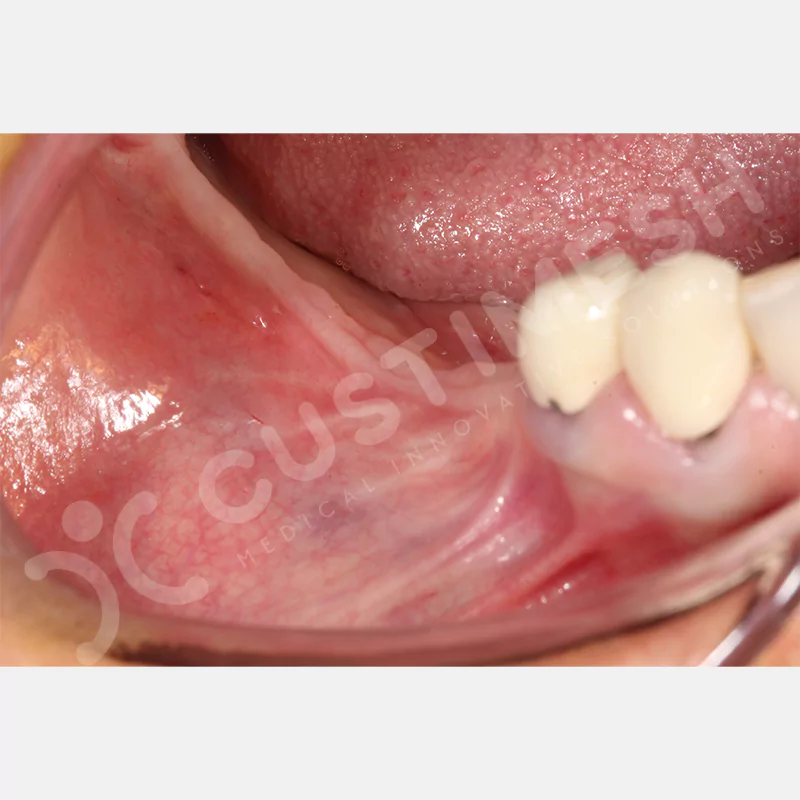

VAKA 3